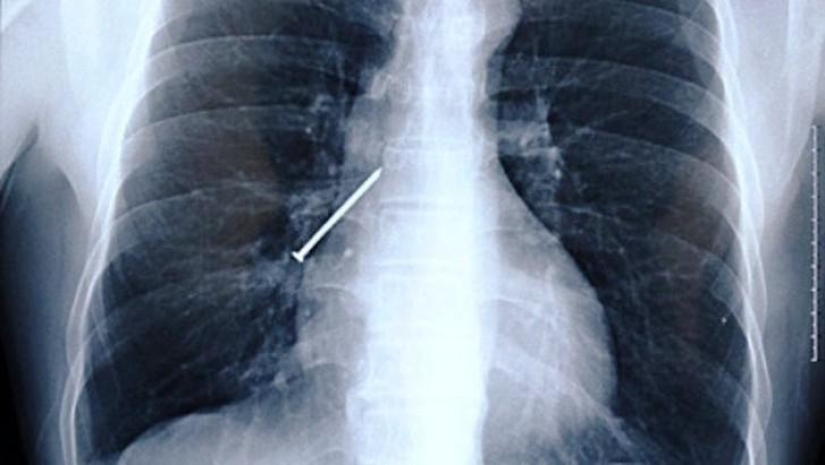

7. Clave.